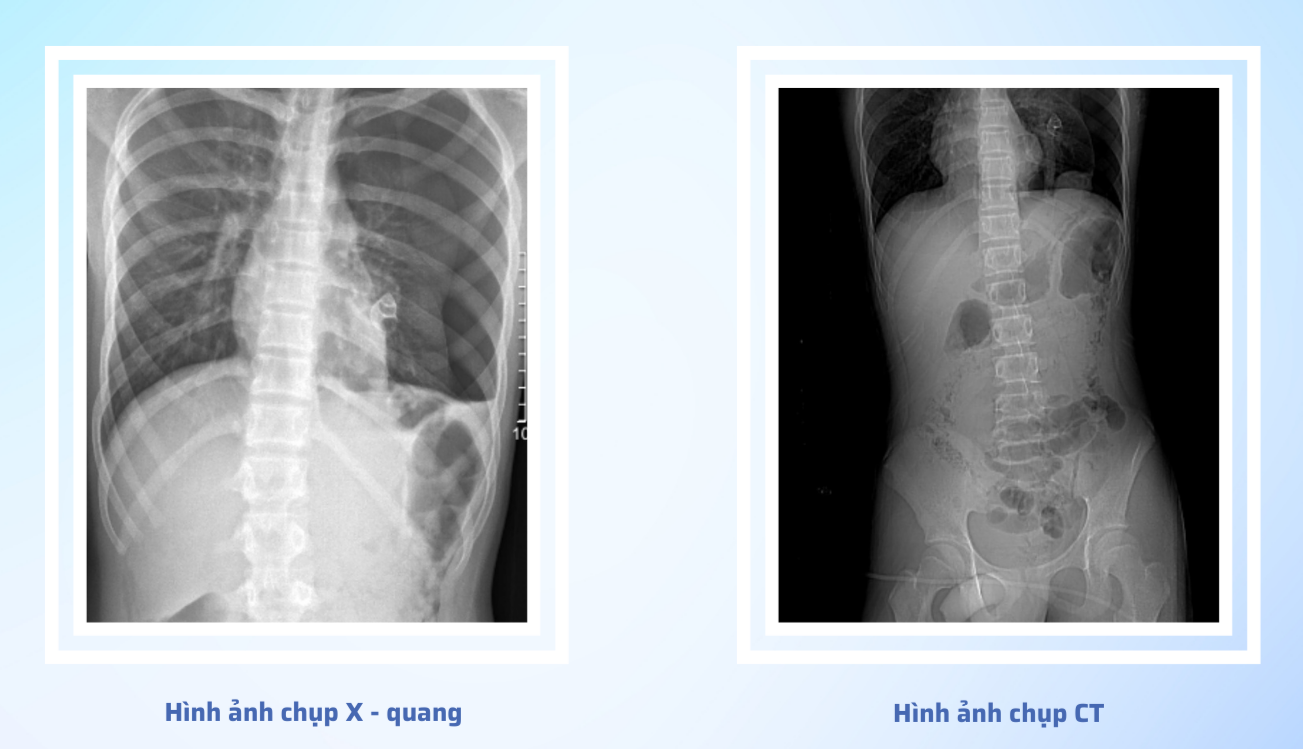

Nhận định đây là tổn thương phức tạp, các bác sĩ khoa Cấp cứu vừa hồi sức vừa hội chẩn các chuyên khoa và chỉ định phẫu thuật cấp cứu cho người bệnh với chẩn đoán: Vết thương tầng sinh môn thấu bụng, ngực.

Tại phòng mổ người bệnh đã được dẫn lưu khoang màng phổi trái. Sau đó được phẫu thuật mở bụng và kiểm tra thấy: Ổ bụng có khoảng 700ml dịch máu loãng, kèm 200gr máu cục. Tổn thương xuyên thủng mặt trước trực tràng, thủng 3 đoạn ruột non, rách mạc treo ruột non, rách mạc treo đại tràng ngang, xuyên thủng dạ dày 2 lỗ, thủng cơ hoành trái khoảng 3cm. Khi kiểm tra qua lỗ thủng cơ hoành trái thấy có rách nhu mô phổi trái, khoang màng phổi trái có dị vật là cành cây gãy và con ốc. Người bệnh đã được lấy bỏ dị vật khoang màng phổi, khâu lại tổn thương nhu mô phổi, lau rửa khoang màng phổi trái, khâu lại lỗ thủng cơ hoành, lỗ thủng dạ dày, cắt 3 đoạn ruột non tổn thương, nối lại các đoạn ruột non. Khâu lỗ thủng trực tràng và đưa quai đại tràng sigma phía trên lỗ thủng ra làm hậu môn nhân tạo. Ca phẫu thuật thành công sau khoảng 5 giờ căng thẳng.